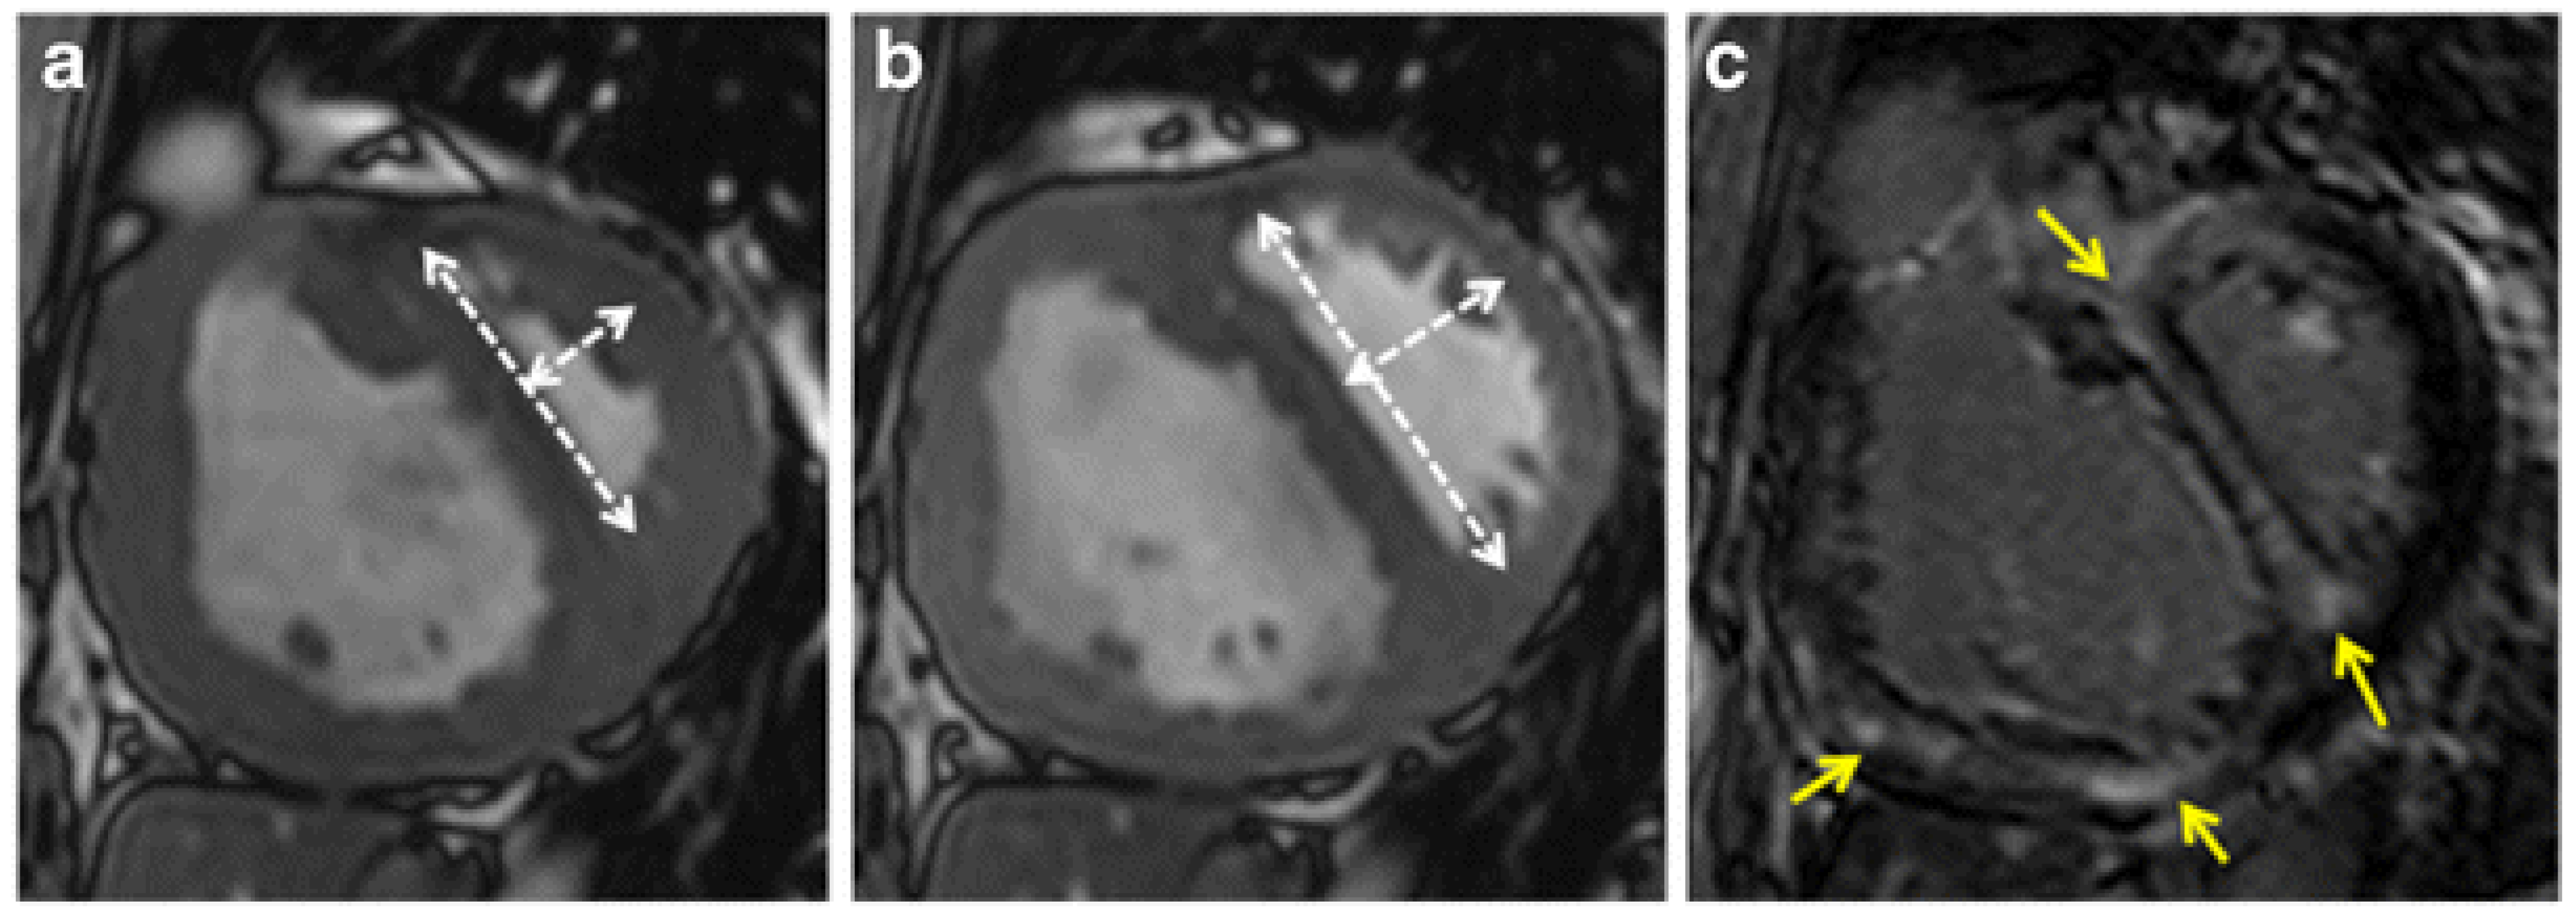

4. Imaging Characteristics on MRI

| 61/Male | Cardiac MRI | Flattened or left-bowing septum during diastole; eccentricity index abnormal | Severe idiopathic pulmonary hypertension [23] |

| 18/Male | Cardiac MRI | Hypertrophied right ventricle and septal leftwards bowing during early diastole | severe idiopathic pulmonary hypertension [23] |

- In Pulmonary Hypertension: Septal flattening is a common feature in moderate to severe PH. Echocardiographic studies have documented D-shaped LV in a substantial fraction of PH patients; Bossone et al. reported that systolic flattening of the interventricular septum was observed in 90% of patients with primary PH, with the majority having pulmonary artery systolic pressures greater than 60 mm Hg [70]. On MRI, almost all patients with severe PH will exhibit some degree of septal flattening. Several studies support this finding. For instance, Pandya et al. demonstrated a strong inverse correlation between septal curvature and mPAP in pediatric patients with PH, with correlation coefficients of −0.81 and −0.85 at baseline and during vasodilator testing, respectively [20]. Similarly, Sciancalepore et al. found that septal curvature values progressively decreased with increasing severity of PH and correlated well with invasive pressures, with r-values ranging from 0.78 to 0.79 [71]. Roeleveld et al. also reported a significant relationship between septal curvature and systolic pulmonary arterial pressure, with a correlation coefficient of 0.77 [21]. Essentially, by the time pulmonary pressure approaches systemic levels, the D-shaped LV emerges [3,72,73]. Thus, epidemiologically, among patients with World Health Organization Group 1 PAH, the Movahed sign could be present in over half of those in NYHA class III–IV or with severe hemodynamics. However, exact prevalence varies by cutoff used and patient mix.